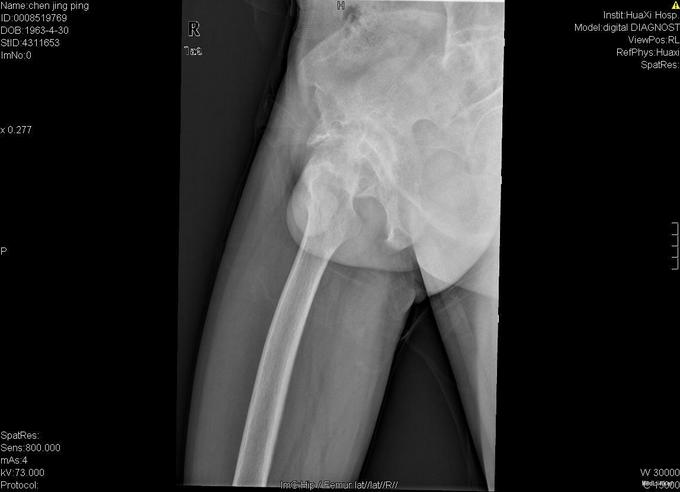

查体:跛行步态,强迫体位,脊柱强直后凸畸形,活动受限。右髋强直畸形,压痛、叩痛,无瘢痕、窦道,无皮损、皮癣,活动受限。双下肢感觉无明显异常。 辅助检查:x线片:脊柱呈"竹节样"改变,腰椎小关节间隙模糊,双侧骶髂关节及右髋关节间隙消失,骨性融合。

诊断:强直性脊柱炎 右髋关节强直 治疗:完善相关检查后在全麻下行右侧全髋关节置换术+髋臼成形术,手术顺利,术后予以抗炎+抗凝+阵痛等治疗。